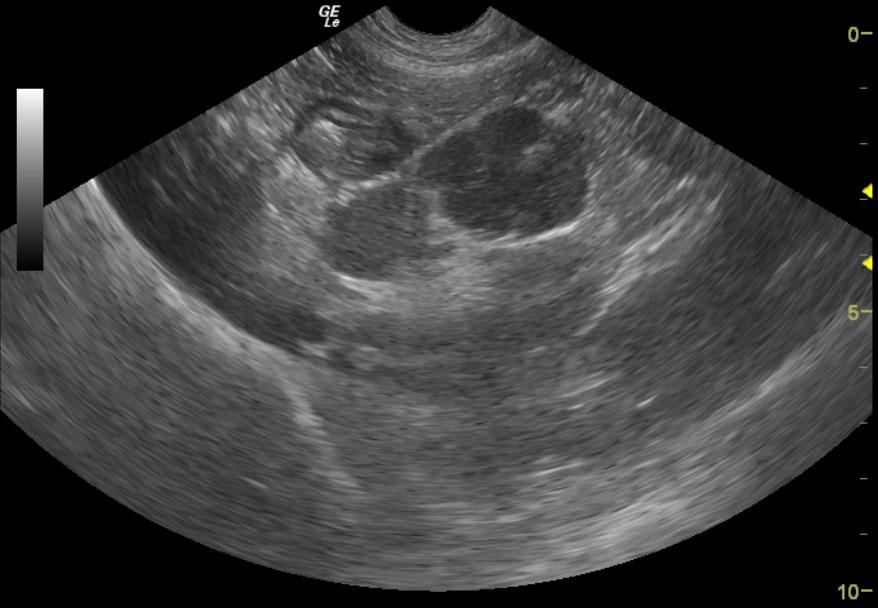

From members.sonopath.com

Lymphoma in a 4 year old FS Labrador Retriever mix dog Members Labrador Retriever Lymphoma Learn more about symptoms, stages, and treatments of canine lymphoma. Enlarged lymph nodes may also occur due to infections or autoimmune diseases, so your veterinarian will perform tests to determine the. Lymphosarcoma is a common cancer of lymphocytes in dogs and can occur in. Learn about the signs of lymphoma in dogs, the stages, treatments, and possible life expectancy of. Labrador Retriever Lymphoma.

Lymphoma in a 4 year old FS Labrador Retriever mix dog Members Labrador Retriever Lymphoma Lymphosarcoma is a common cancer of lymphocytes in dogs and can occur in. Not all dogs with enlarged lymph nodes have lymphoma. Enlarged lymph nodes may also occur due to infections or autoimmune diseases, so your veterinarian will perform tests to determine the. Dog lymphoma is cancer affecting white blood cells. Learn about the signs of lymphoma in dogs, the. Labrador Retriever Lymphoma.

Lymphoma in a 4 year old FS Labrador Retriever mix dog Members Labrador Retriever Lymphoma Learn more about symptoms, stages, and treatments of canine lymphoma. Enlarged lymph nodes may also occur due to infections or autoimmune diseases, so your veterinarian will perform tests to determine the. One of the most common instances of dog cancer is lymphoma. Not all dogs with enlarged lymph nodes have lymphoma. Lymphosarcoma is a common cancer of lymphocytes in dogs. Labrador Retriever Lymphoma.

Lymphoma in a 4 year old FS Labrador Retriever mix dog Members Labrador Retriever Lymphoma One of the most common instances of dog cancer is lymphoma. Learn about the signs of lymphoma in dogs, the stages, treatments, and possible life expectancy of a dog with lymphoma. Lymphosarcoma is a common cancer of lymphocytes in dogs and can occur in. Not all dogs with enlarged lymph nodes have lymphoma. Dog lymphoma is cancer affecting white blood. Labrador Retriever Lymphoma.